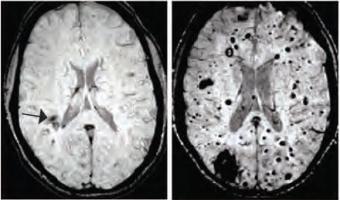

ÉPILEPSIE : Localiser la source des crises, entre 2 convulsions

Actualité publiée le 24/08/2016ÉPILEPSIE: Un cerveau virtuel qui reconstitue les crises du patient

Actualité publiée le 02/08/2016